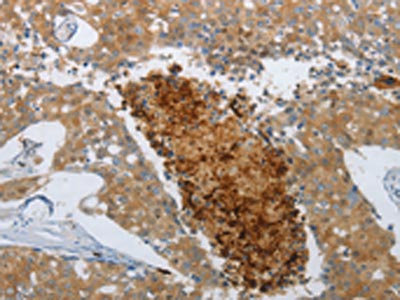

The image on the left is immunohistochemistry of paraffin-embedded Human breast cancer tissue using CSB-PA084270(NGFR Antibody) at dilution 1/50, on the right is treated with synthetic peptide. (Original magnification: ×200)

The image on the left is immunohistochemistry of paraffin-embedded Human tonsil tissue using CSB-PA084270(NGFR Antibody) at dilution 1/50, on the right is treated with synthetic peptide. (Original magnification: ×200)